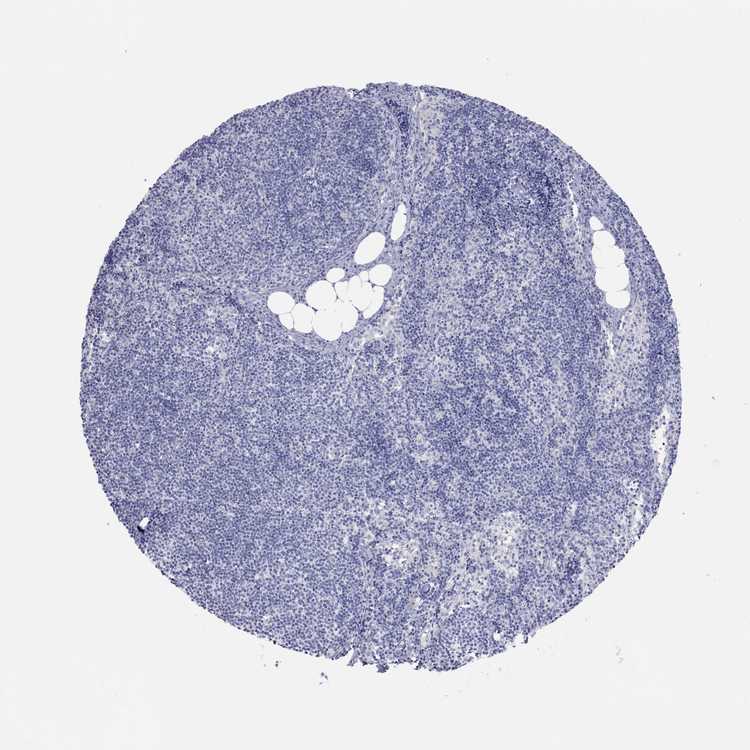

TISSUE PRIMARY DATA LYMPH NODE Show tissue menu

Lymph node

LYMPH NODE - Antibody stainingi

Antibody staining in the annotated cell types in the current human tissue is reported as not detected, low, medium, or high, based on conventional immunohistochemistry profiling in selected tissues. This score is based on the combination of the staining intensity and fraction of stained cells.

Each image is clickable and will lead to virtual microscopy that enables deeper exploration of all samples and also displays staining intensity scores, fraction scores and subcellular localization as well as patient and tissue information for each sample.

Antibody HPA066228Antibody CAB037086

Germinal center cells Not detectedNot detected

Non-germinal center cells Not detectedMedium